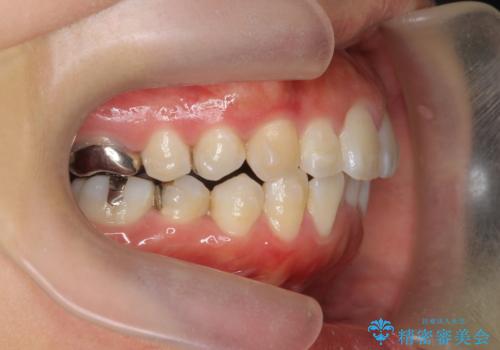

前歯の角度を改善するマウスピース矯正

- 前歯の角度・重なりの改善を求めて矯正治療を希望され来院されました。

通常このような場合、小臼歯を4本抜去しワイヤー矯正を行う治療計画も検討されますが、今回は側方に拡大できる骨量が十分に存在したため抜歯をしない矯正治療の計画を立てます。

しっかりと拡大を行い、IPRも併用したことで歯並びと前歯の角度を大幅に改善することができました。